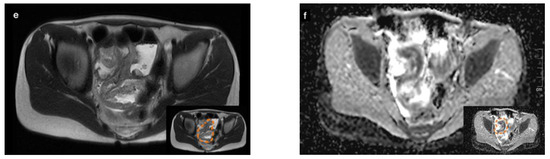

3. Case 2

3.3. Diagnostic Evaluation